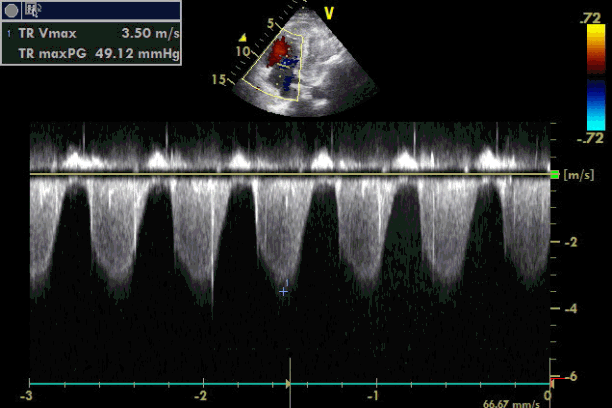

Emergency transesophageal echocardiography (TEE) was performed. The test revealed a hypokinetic dilated right ventricle (RV) and a D-shaped left ventricle (LV) (Figure 2). LV systolic dysfunction was noted without inferior vena cava (IVC) collapsibility. Tricuspid regurgitation was found with 49 mmHg pressure gradient (Figure 3). Considering the decreased EtCO2, elevated PaCO2, and TEE findings, PTE was suspected. Cardiopulmonary resuscitation until return of spontaneous circulation was repeated 3 times. HR was maintained at 120 beats/min, SBP at 150 mmHg, and SpO2 at 70%. Following consultation with cardiology and neurosurgery, we decided to use thrombolytics after diagnosis by multidetector computed tomography (MDCT). MDCT revealed occlusion of both pulmonary arteries with multiple pulmonary thromboembolisms and atelectasis in both lungs, consistent with a diagnosis of acute PTE (Figure 4). DVT was not observed elsewhere. The D-dimer level from a sample obtained in the operating room was above 3,200 ng/ml and troponin I was 0.02 ng/ml.